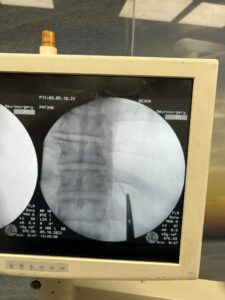

وتابعت، أنه تم حجز المريض بالقسم وتجهيزه لعملية سريعة، جرى فيها الاستعانة بجهاز الأشعة الملحق بغرف العمليات (C-arm)، حيث تم تحديد مكان الإبرة والفتح الجراحي عليها مباشرة، واستخراجها بنجاح ،ولكن على هيئة قطع منكسرة بسبب الصدأ، نظرا لبقائها طوال هذه المدة.